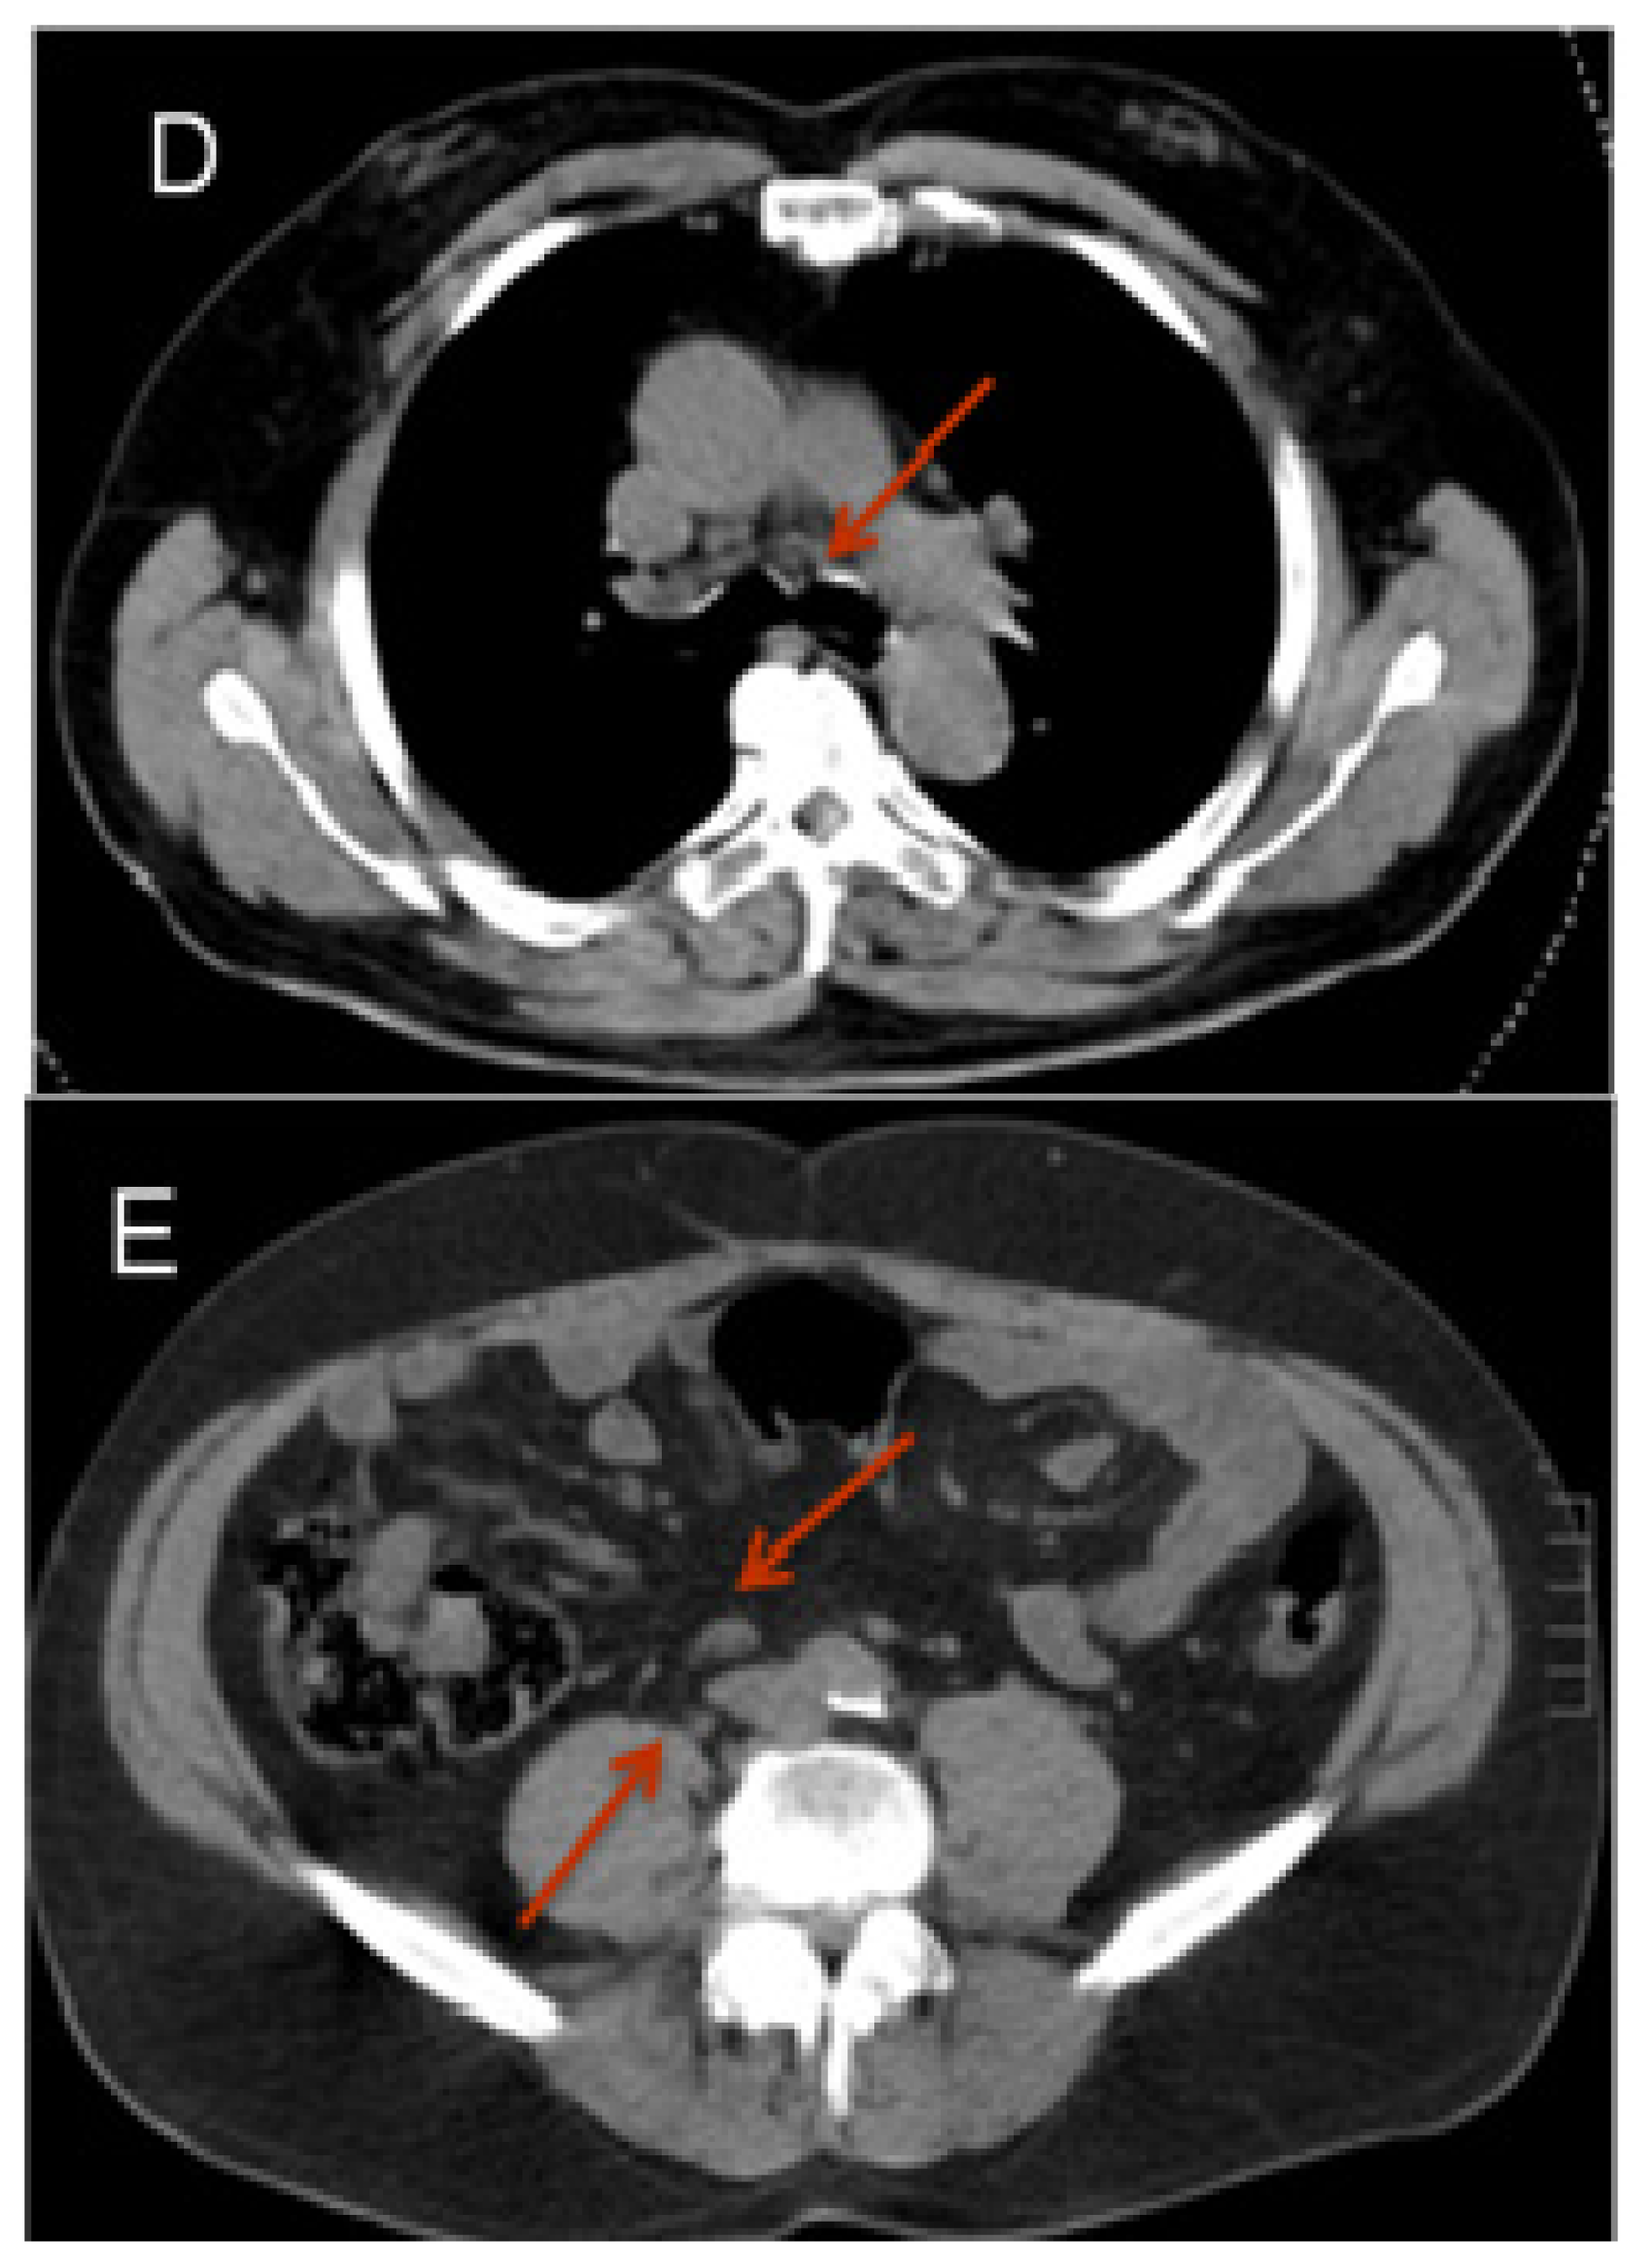

Figure 2.

68Ga-PSMA-PET-CT. Patient with prostate cancer (status after brachy-therapy and bilateral iliac lymph node dissection, current PSA 21 μg/L). PET images were acquired after the administration of 68GA-PSMA-Ligand (60 min thereafter). The figure shows fused images (PET-CT): On the coronal view (A) a pathologic isotope uptake in multiple lymph nodes in the right para-iliac region and infra-carinal (mediastinum) is clearly visible; the corresponding transversal images show the para-iliac (B) and infra-carinal (C) lymph nodes with elevated uptake of the tracer. The corresponding transversal native CT images present these suspect structures (D,E) as normal sized lymph nodes (marked by red arrows).